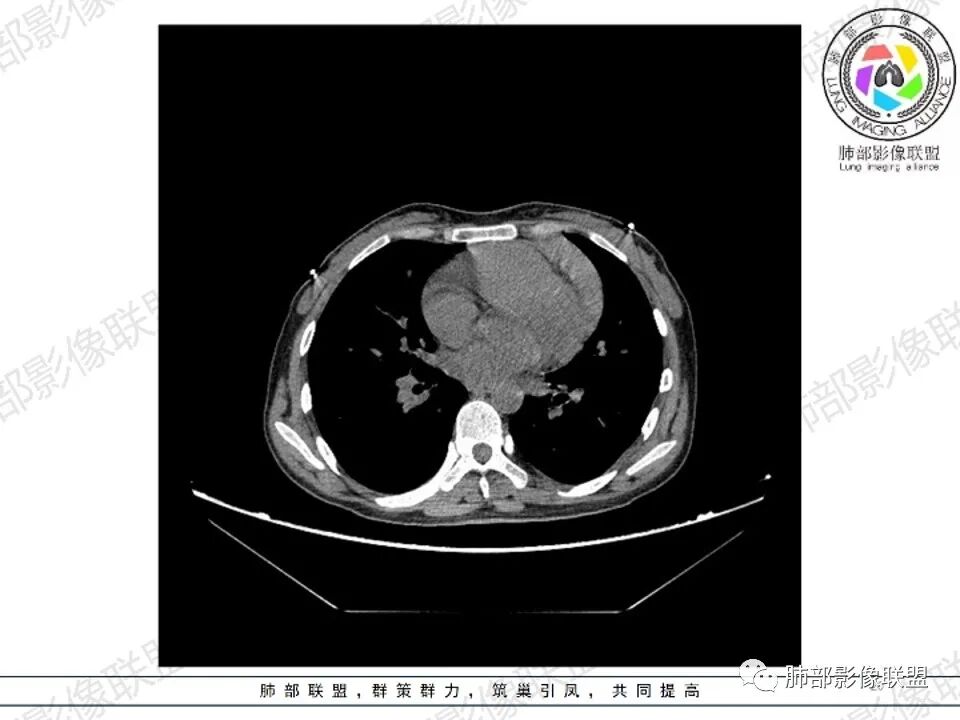

纵隔多发结节堆积 塑型生长  质软 边界不清 强化不均  双侧腋窝淋巴结肿大

年轻女性,贫血伴乏力,前纵隔占位,多发结节融合成块,爬孵感,边界模糊,不均匀强化,中心坏死,内可见血管造影,部分侵犯心包,双侧腋窝多发肿大淋巴结,首先考虑淋巴瘤

年轻女性,贫血,CT示前纵隔团片状软组织占位,多结节堆积感,塑形生长,边界欠清,包绕大血管及心包,增强明显不均匀强化,内见血管漂浮。纵隔4R,5,7区及双侧腋窝多发肿大淋巴结,综合考虑为淋巴瘤可能

前纵隔不规则肿块,多结节融合,边界欠清,延周围脂肪间隙生长,包绕主动脉及肺动脉血管,平扫密度欠均匀,增强扫描可见多发低密度坏死,并可见一条血管穿行,腋窝多发大小不等淋巴结肿大,年轻女性,考虑恶性:淋巴瘤,胸腺癌,肉瘤,浆细胞瘤

女,27,间断头晕、乏力3年,左眼视物模糊2月。贫血。胸部CT:前纵隔不规则肿块,多结节融合,边界不清,沿主动脉及肺动脉间隙生长,平扫密度欠均匀,增强扫描可见多发低密度坏死,纵隔血管供血穿行,腋窝多发大小不等淋巴结肿大。考虑恶性病变,胸腺癌?肉瘤?淋巴瘤?鉴别胸腺瘤、结节病等。

前纵隔和双侧腋窝多发的淋巴结肿大,前纵隔为甚,融合呈中等强化,部分坏死呈低密度,包埋肺动脉主干和左心缘,融合斑块状,内见血管飘浮特点,前纵隔脂肪间隙混浊,首选淋巴瘤!

CT:定位纵膈病变,前中纵隔多发肿块,质软,塑形,密度不均匀,边界清楚。增强不均匀强化,坏死边界清楚,血管漂浮征。双侧腋下多组淋巴结肿大,明显异常强化。

2.影像显示前纵隔不规则块状影,依势贴附心脏大血管旁,密度不均,边界不甚清楚,有结节融合感。

3.病灶轻度不均匀强化,可见血管穿行,散在液性低密度区。

双肺门未见肿大淋巴结。

4.双侧腋窝区见增大淋巴结,边界清楚。

1.年轻女性,前纵隔不规则块状影,密度不均,边界不甚清楚,有结节融合感,轻度不均匀强化,可见血管穿行,最常见最符合的无疑是淋巴瘤!